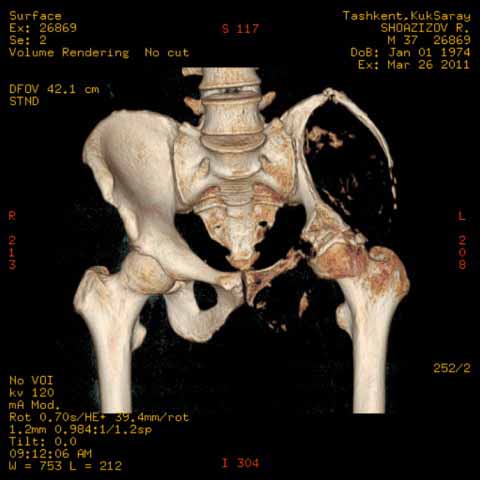

Могу пока выложить еще снимки и показать хронологию данного процесса и его прогрессирование, первый снимок был 2011 года. Вот этот 2009

И 2010 год

Также структуру поражения кости можно увидеть на обычных рентгенограммах таза или Компьютерно-Томографических срезах. Трехмерные снимки, кроме красивой картины, не добавляют информации, и самым главным информативным является МРТ, которая покажет структуру ячеек.